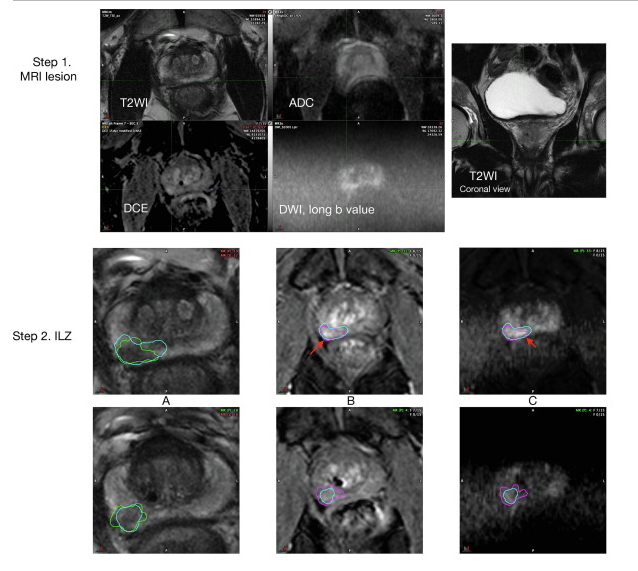

La interpretación de mpMRI se ha mejorado mediante la adopción de las pautas PI-RADSv2. En PI-RADSv2, se asigna una puntuación de 1 a 5 a cada lesión. Si la lesión está en el PZ, la puntuación depende en gran medida de la puntuación DWI y menos en T2W y DCE-MRI. (figura 2)

Fig. 2. European Urology Open Science, Volume 72, February 2025, Pages 36-41

El problema de la subestimación del volumen tumoral puede mitigarse mediante el uso de un margen de tratamiento de al menos 9 mm alrededor de las lesiones visibles en mpMRI (11), teniendo en consideración la dirección de la potencial diseminación. (figura 3). No es necesario decir que un margen de 9 mm es muy extenso, y se necesita más trabajo para garantizar que los tamaños de las lesiones mpMRI y las zonas de tratamiento estén mejor delineadas, especialmente si esto se va a utilizar como una modalidad de diagnóstico para planificar y monitorear la terapia focal.

Fig 3. European Urology Open Science, Volume 72, February 2025, Pages 36-41